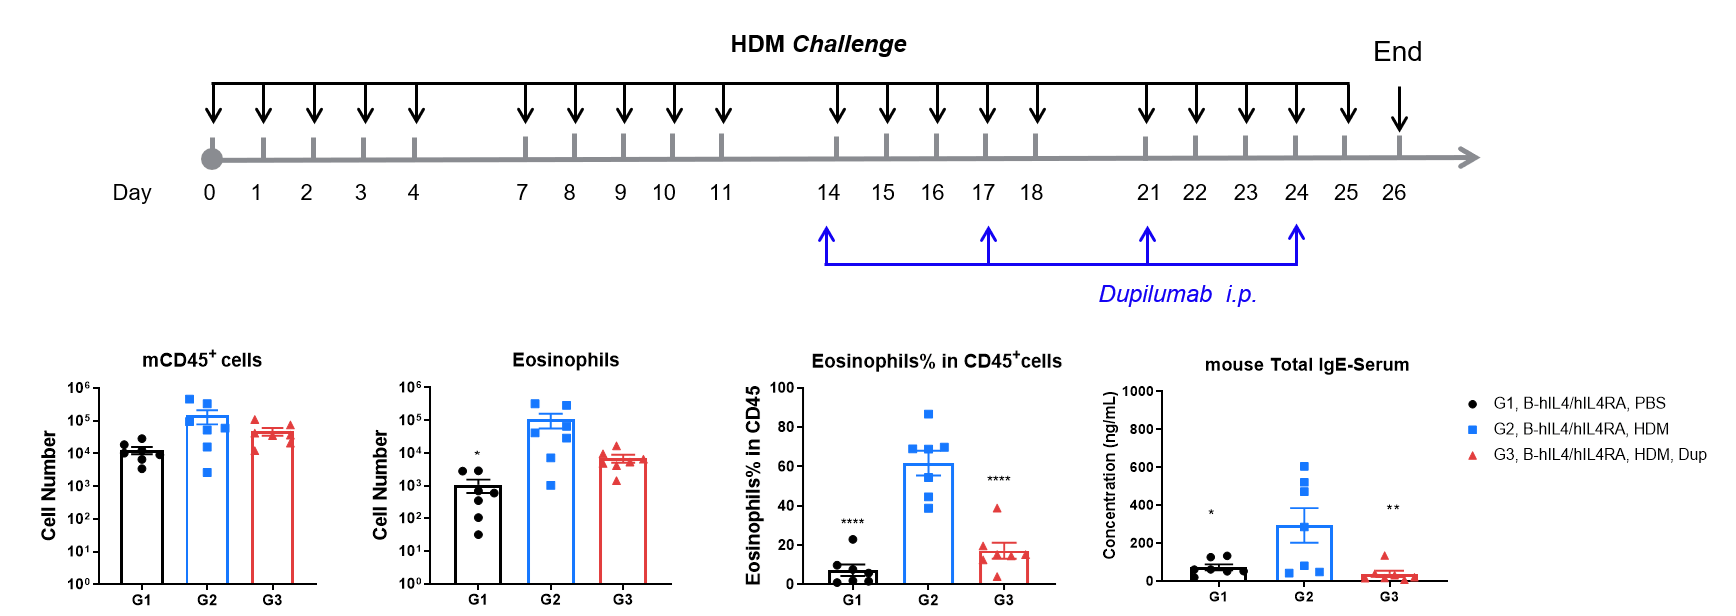

Efficacy of anti-human IL-4R antibody (dupilumab) in HDM-induced asthma model of IL-4 and IL-4 receptor humanized (B-hIL4/hIL4R) mice. Following HDM sensitization and challenge, G2 mice showed significantly increased CD45⁺ leukocyte counts, eosinophil numbers, and eosinophil proportions in bronchoalveolar lavage fluid (BALF) compared to G1 controls, indicating successful asthma model induction. Treatment with in-house dupilumab (25 mg/kg) significantly reduced CD45⁺ cells and eosinophils. At endpoint, serum total IgE levels measured by ELISA were also elevated in G2 and significantly reduced after dupilumab administration, confirming therapeutic efficacy of IL-4R blockade.